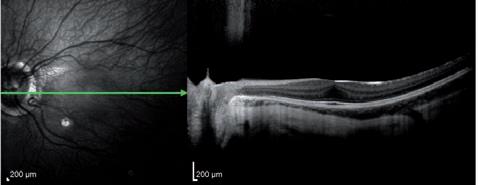

Obr. 1.5 Řezy duhovkou pravého oka pomocí optické koherenční tomogra e. Horní snímek dokumentuje chybějící část předního listu duhovky, dolní snímek zobrazuje adherence duhovky k embryotoxonu